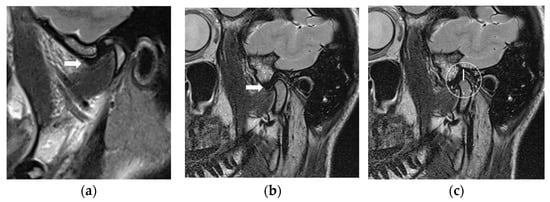

2.2.3. Magnetic Resonance Imaging

| Joint | MRI Slices | Before | After | |||

| Right | 1 | 18 | 10:21 ± 0:30 | 18 | 12:00 ± 0:20 | 0.0002 |

| 2 | 17 | 10:19 ± 0:29 | 18 | 12:01 ± 0:19 | 0.0008 | |

| 3 | 17 | 10:19 ± 0:29 | 17 | 12:03 ± 0:18 | 0.0006 | |

| 4 | 17 | 10:19 ± 0:29 | 17 | 12:03 ± 0:18 | 0.0006 | |

| 5 | 15 | 10:30 ± 0:27 | 16 | 12:03 ± 0:18 | 0.0003 | |

| 6 | 15 | 10:32 ± 0:26 | 16 | 12:03 ± 0:18 | 0.0003 | |

| 7 | 13 | 10:32 ± 0:28 | 15 | 12:04 ± 0:19 | 0.0005 | |

| Left | 1 | 19 | 10:34 ± 0:30 | 19 | 12:03 ± 0:17 | 0.0001 |

| 2 | 18 | 10:31 ± 0:28 | 18 | 12:01 ± 0:16 | 0.0002 | |

| 3 | 18 | 10:33 ± 0:27 | 18 | 12:01 ± 0:16 | 0.0001 | |

| 4 | 17 | 10:31 ± 0:28 | 17 | 12:01 ± 0:16 | 0.0009 | |

| 5 | 15 | 10:36 ± 0:23 | 16 | 12:01 ± 0:17 | 0.0002 | |

| 6 | 15 | 10:28 ± 0:28 | 16 | 12:00 ± 0:18 | 0.0005 | |

| 7 | 13 | 10:25 ± 0:29 | 15 | 11:58 ± 0:23 | 0.0005 | |